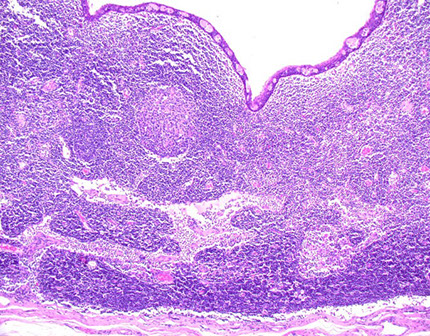

Subacute necrotizing sialadenitis of the left palate c focal acinar necrosis (stars)

Subacute necrotizing sialadentiis

Necrotizing sialometaplasia of the palate with pseudoepitheliumatous hyperplasia (PEH)